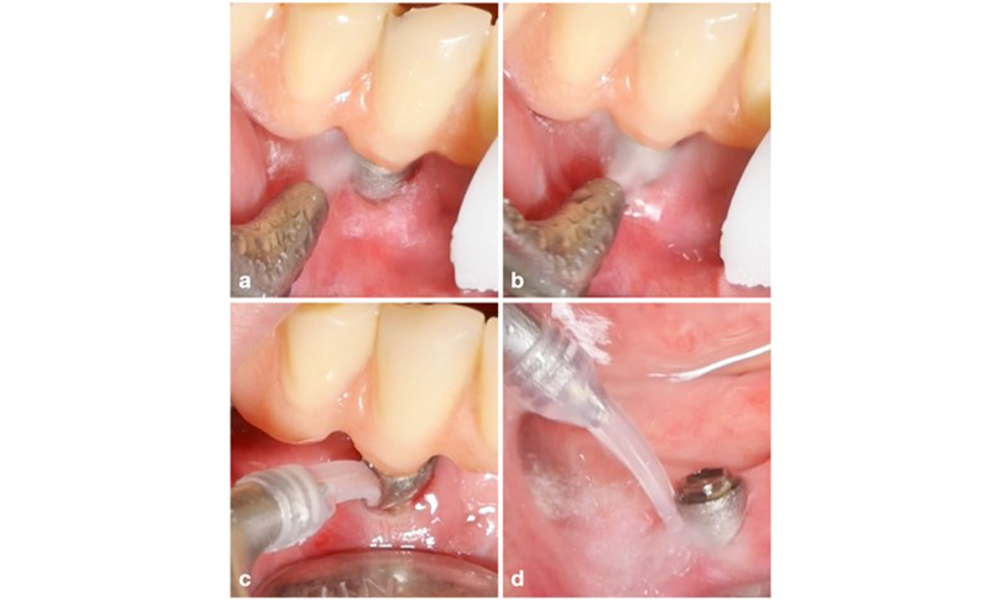

Изборът на средство зависи от клиничните обстоятелства, като например разликата между зъбен камък и мека плака. По този начин, в случаите със зъбен камък първо трябва да се използват титаниеви или пластмасови кюрети или специални накрайници за ултразвукови скалери, последвани от използването на устройство за въздушно полиране (фигура 7). В случаите само с натрупване на мека плака може да е достатъчно само въздушно полиране. Устройствата за въздушно полиране са лесни за ползвателя и пациента и са поне толкова ефективни, колкото стандартните инструменти (Schwarz et al. 2015a).

Лечението на периимплантит при импланти, оценени като лечими, се състои от нехирургична фаза, която често е последвана от хирургична интервенция. Нехирургичните процедури са подобни на тези, прилагани за лечение на периимплантатен мукозит. Лабораторните експерименти показват, че устройствата за въздушно полиране със субгингивални накрайници изглежда осигуряват определени предимства по отношение на отстраняването на биофилм в сравнение с ръчните или ултразвукови инструменти (Herrera et al. 2023; Moharrami et al. 2019; Ronay et al. 2017) ( фигура 9).